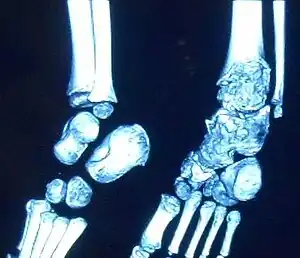

Trevor disease in a nine-year-old girl: talus

3D CT image of Trevor's disease of the ankle and talus.

This disorder is rare, and is characterised by an asymmetrical limb deformity due to localized overgrowth of cartilage, histologically resembling osteochondroma. It is believed to affect the limb bud in early fetal life. The condition occurs mostly in the ankle or knee region and it is always confined to a single limb. This usually involves only the lower extremities and on medial side of the epiphysis. It is named after researcher David Trevor.[1]

Trevor disease was first described by the French surgeon Albert Mouchet and J. Belot in 1926. In 1956, the name "dysplasia epiphysealis hemimelica" was proposed by Fairbank.[1] The usual symptoms are the appearance of an osseous protuberance, on one side of the knee, ankle or foot joint which gradually increases Radiologically,[14] the condition shows a nonuniformity of growth and multiple unconnected ossification centers around the epiphyses.[8]